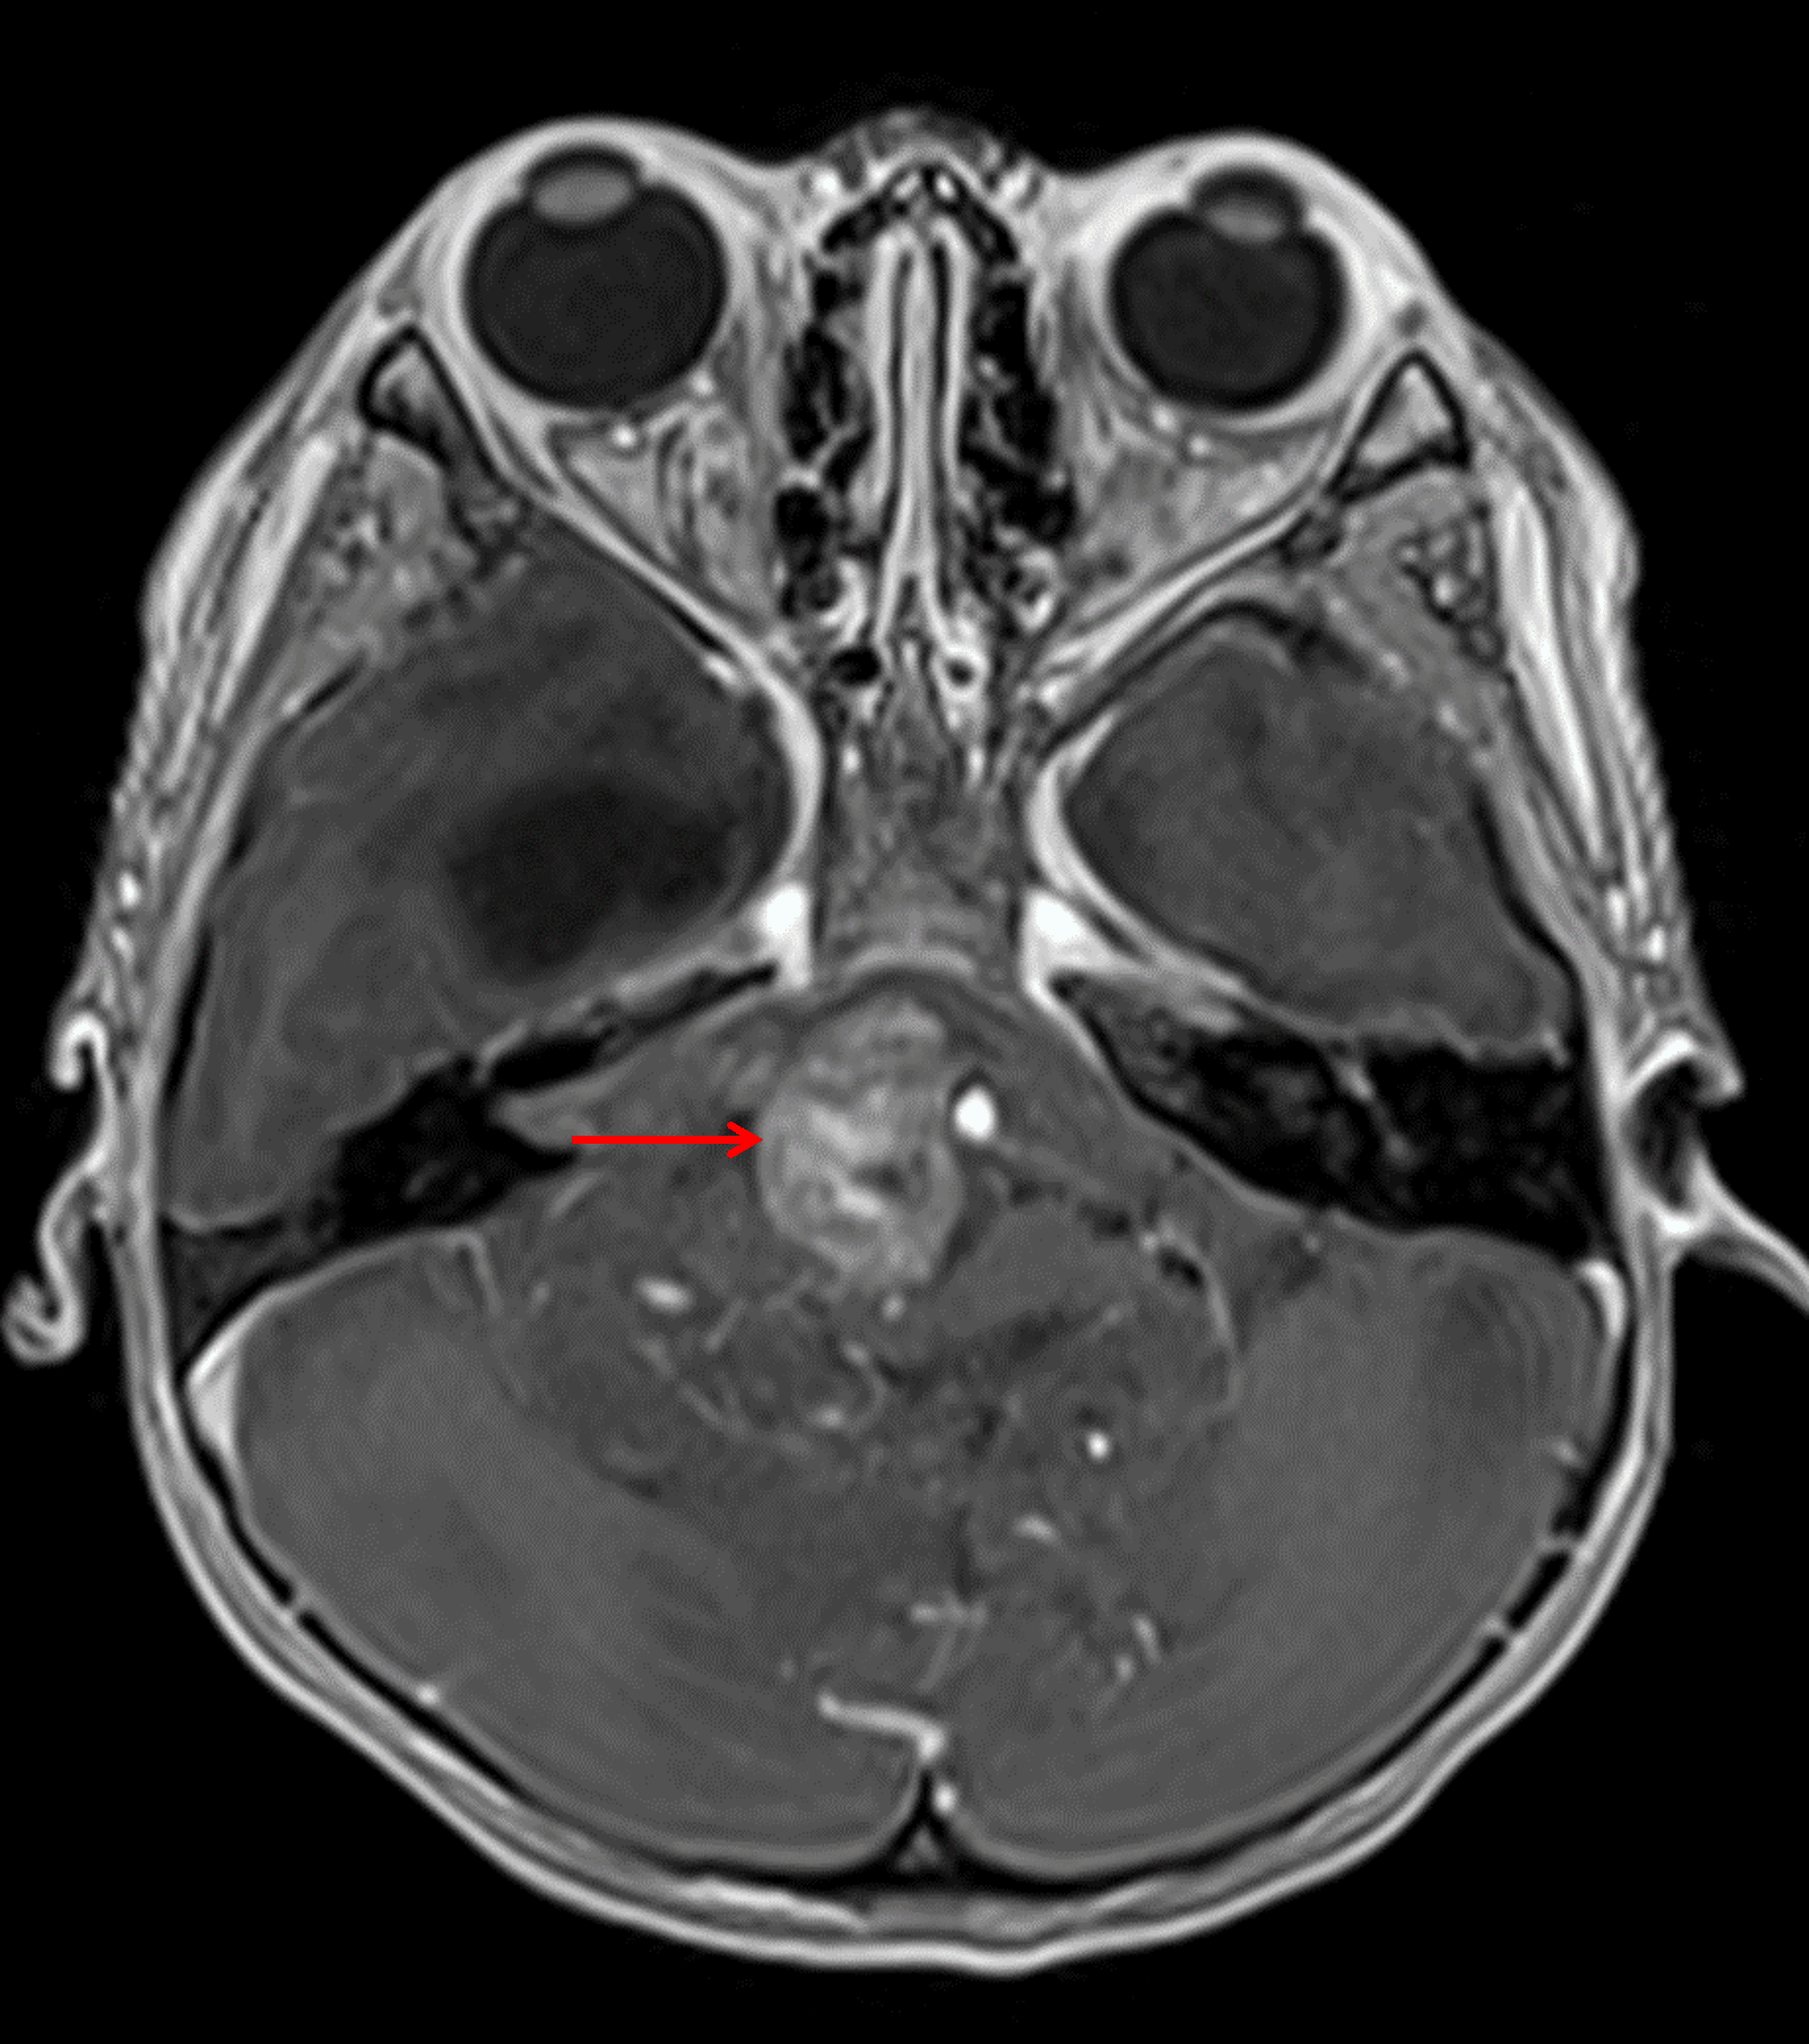

Heterogeneous areas of internal enhancement, including in the prepontine tumor component (red arrow).